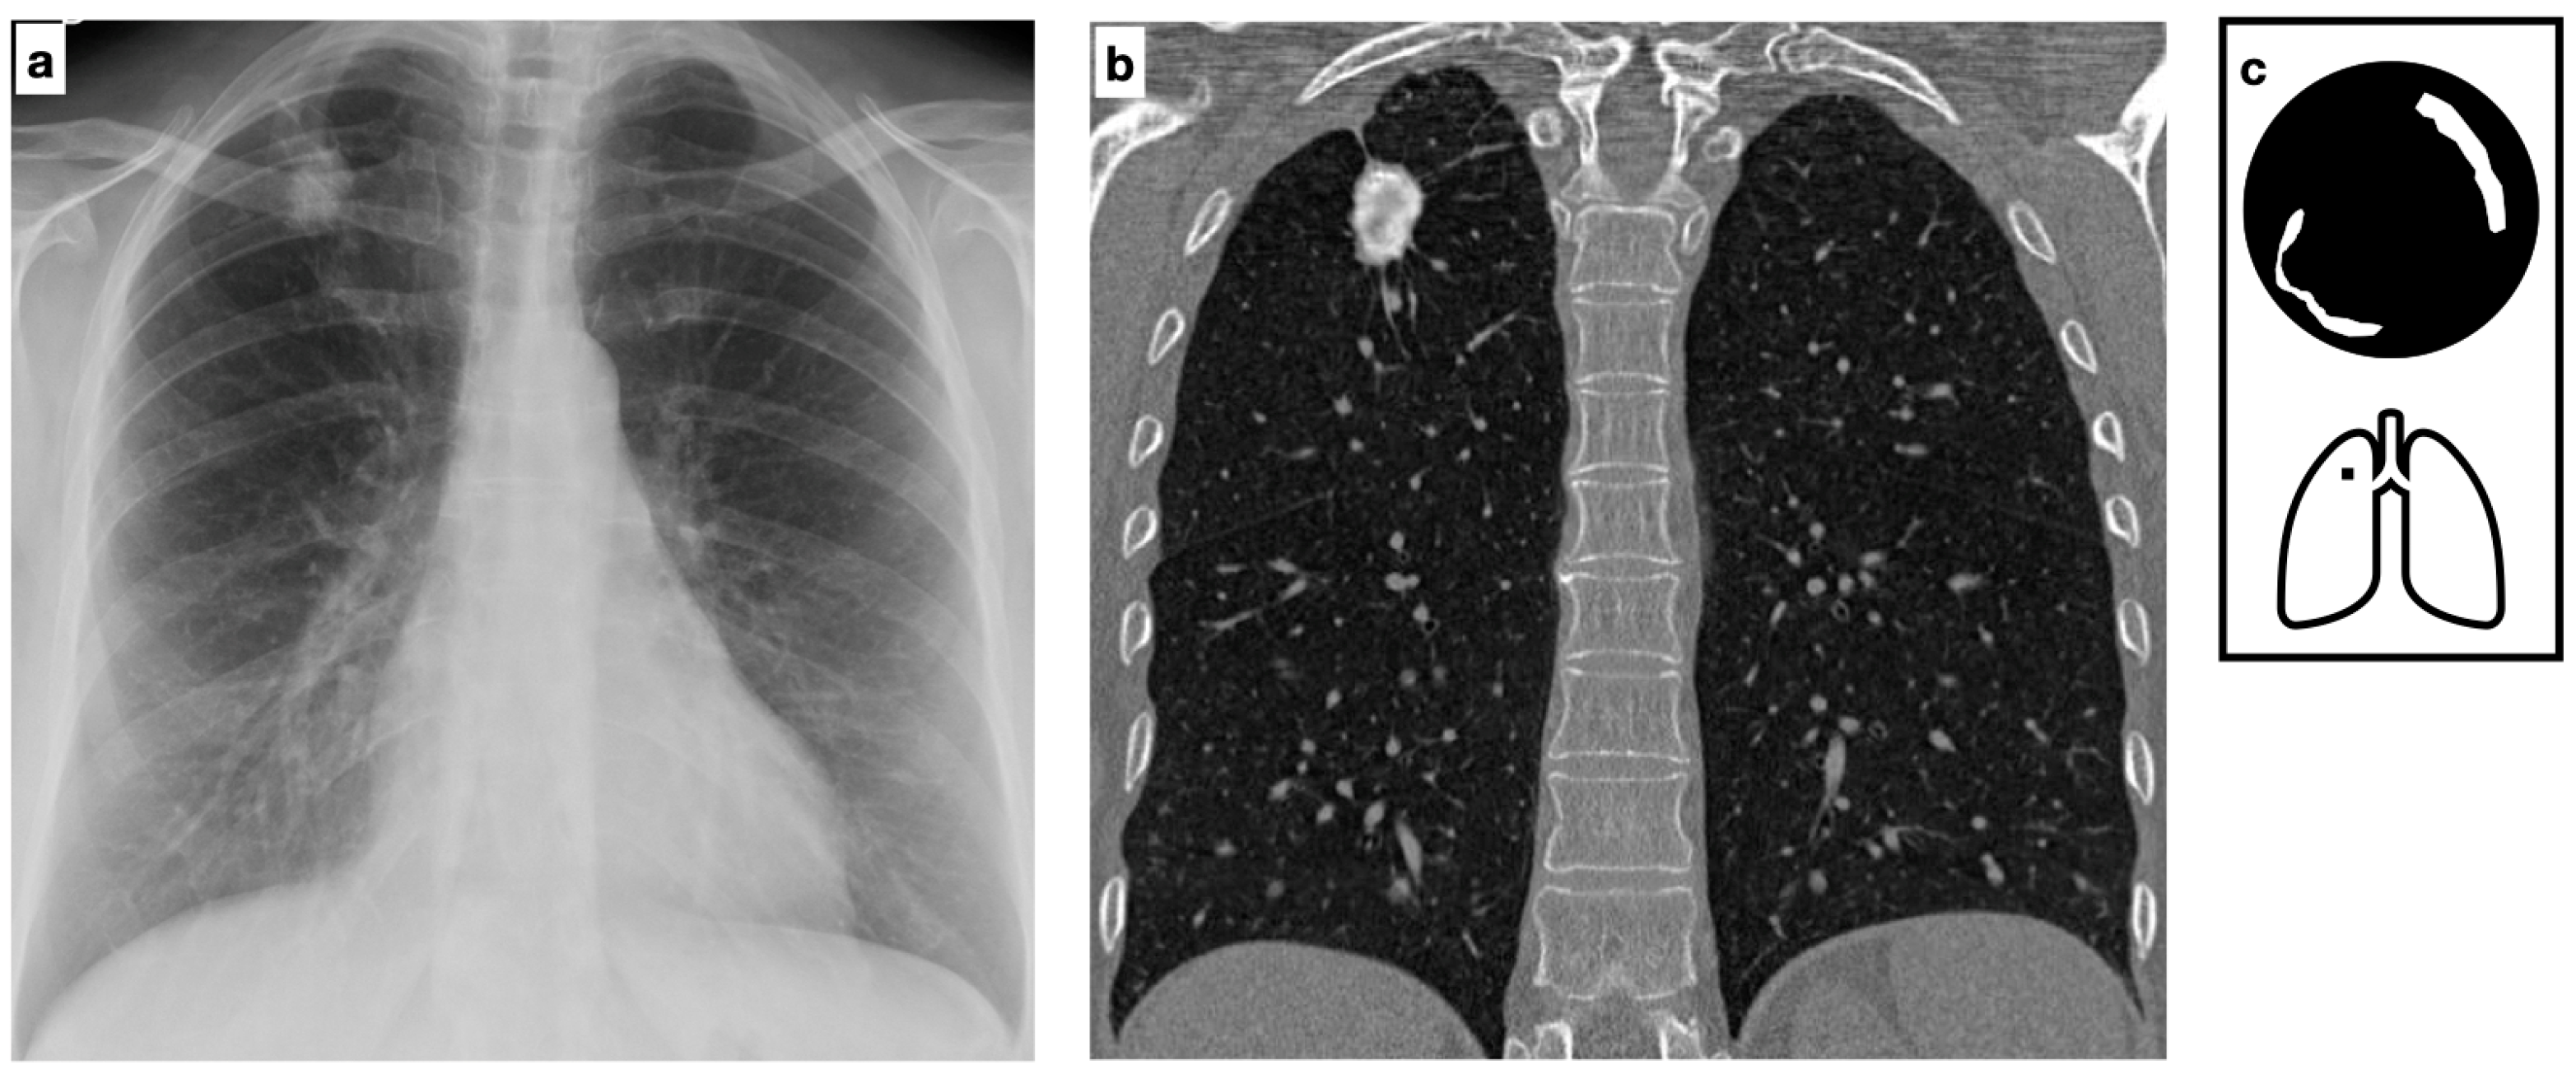

Figure 5.

Patient with previous history of severe varicella pneumonia. HRCT shows bilateral diffuse ill-defined calcified nodules. Scattered diffuse micronodular calcifications are an uncommon late sequela of VZV pneumonia (a,b). Pattern of calcification (c).